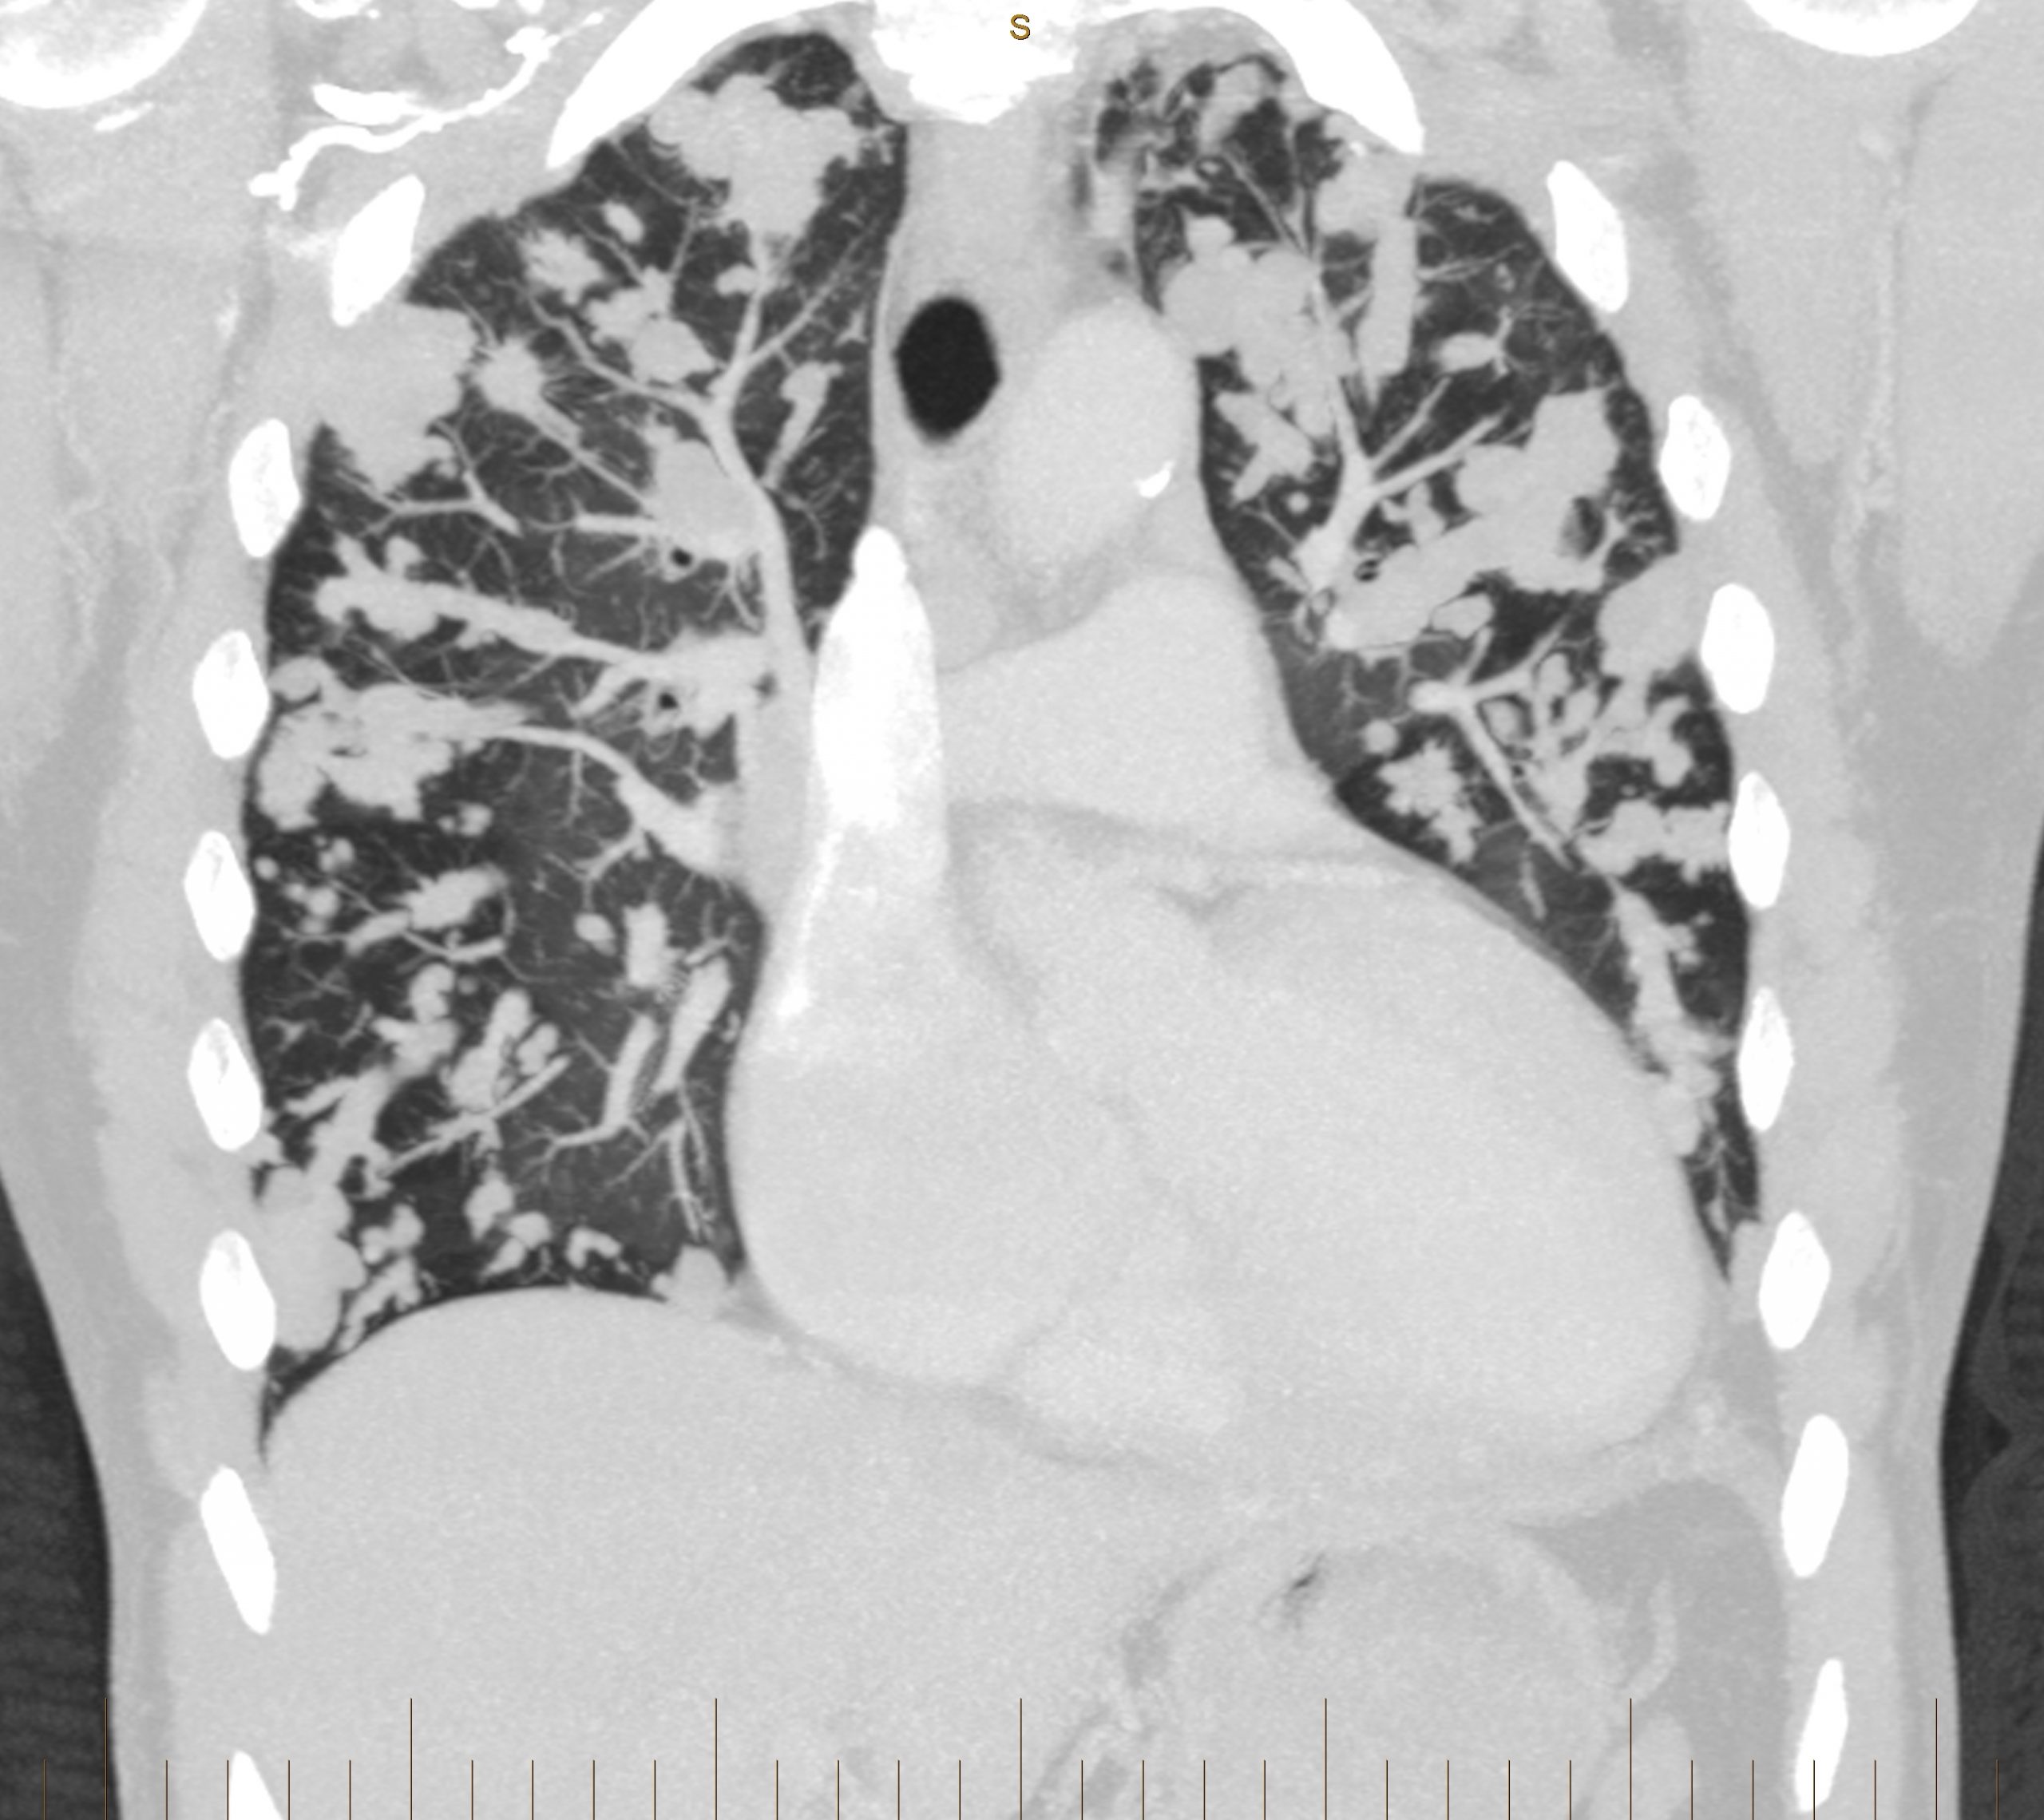

Figure 3

CT pulmonary angiogram: coronal view. Multiple hydatid masses within the pulmonary vasculature.

Multiple lobulated areas within the pulmonary vasculature from extensive dissemination of hydatid disease originating from the RV.